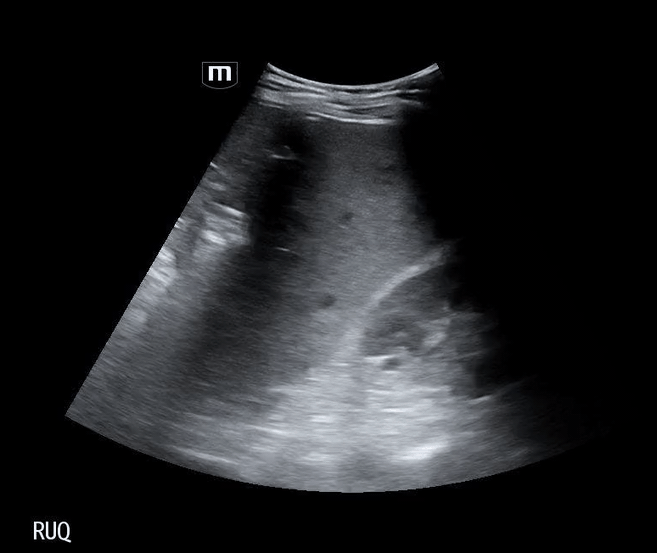

The patient was a limited historian and reported multiple complaints which included chest pain, left lower extremity pain, rectal pain, and cough. Due to the unclear history and concern for potential underlying pathology, a bedside FAST ultrasound was obtained.

Using the curvilinear probe, we see a well-defined, round lesion within the liver parenchyma on the right lower quadrant US: